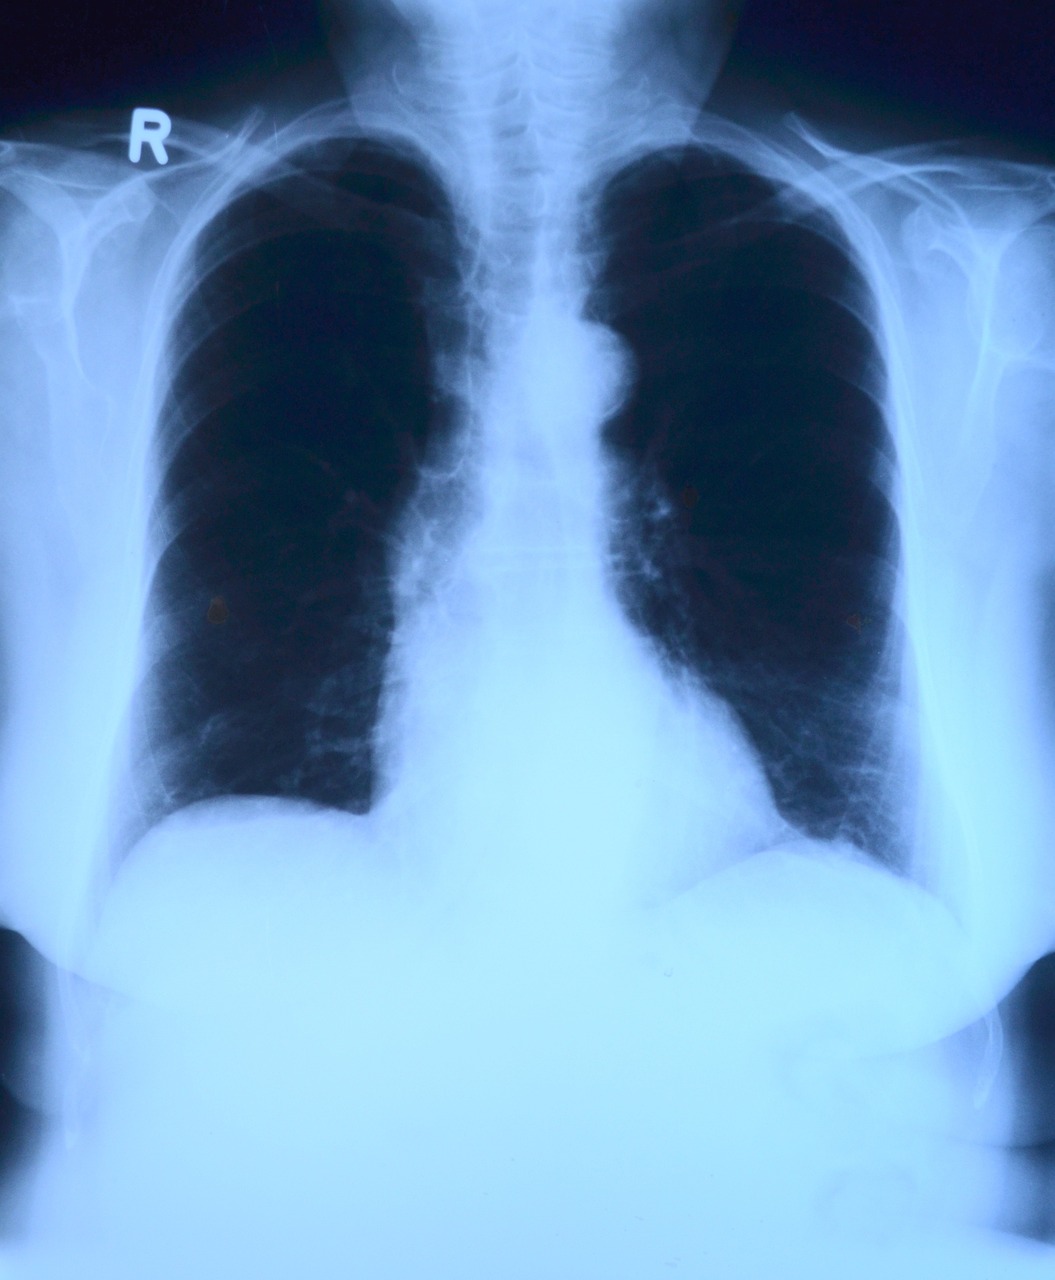

Invitan a identificar los síntomas de la tuberculosis pulmonar

Síntomas como tos con flemas que prevalezca por más de 15 días, dolor torácico, cansancio o debilidad muscular que no mejora con el reposo, pérdida de peso, fiebre o sudoración nocturna y dificultad respiratoria sugieren la presencia de tuberculosis pulmonar, detalló el coordinador de salud pública en el Instituto Mexicano del Seguro Social (IMSS) en...